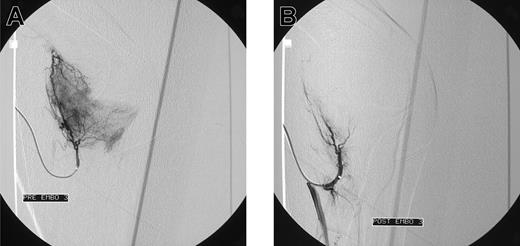

Initial angiograms demonstrated a blush, indicative for hyperemic tissue as cause of bleeding in 15 patients (Figure 1A-B); in 2 patients a false aneurysm was observed (Figure 2A-B); in one patient a true aneurysm was observed; and in 3 patients an arteriovenous shunt in combination with an aneurysm was observed. In all these cases embolization of the feeding arteries was performed. However, in some cases, it was not possible to embolize all the bleeding arteries. In 2 patients, the cause of bleeding could not be localized (one patients with postoperative knee bleeding and one with spontaneous elbow bleeding) and embolization was not performed.

Blush in a patient with elbow bleeding. Angiogram shows massive blush in a patient with recurrent spontaneous elbow bleeding before (A) and after (B) embolization.